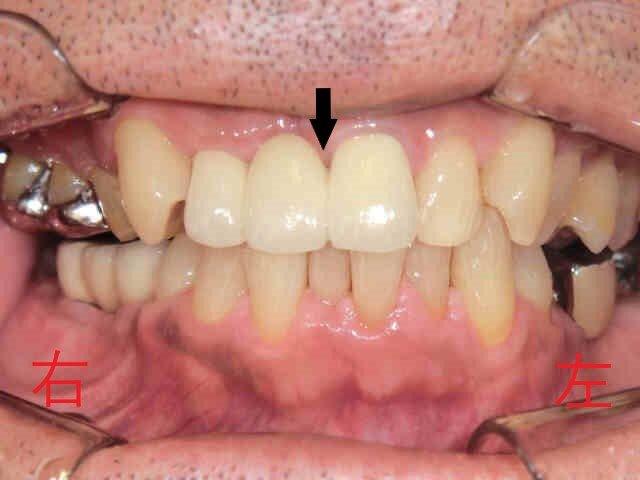

左上の写真は初診時の口腔内写真、右上はインプラント治療を含めた全ての治療が完了した後の写真です。

さらに別の写真では、左上前歯(黒色矢印)に大きな虫歯があり、穴があいている様子が確認されました。治療後は、メタルボンド(セラミックを使用した被せ物)によるブリッジを装着しています。これは、保険適用の素材に比べて変色しにくく、歯垢(プラーク)も付着しにくいため、虫歯や歯周病の予防にも配慮された素材です。